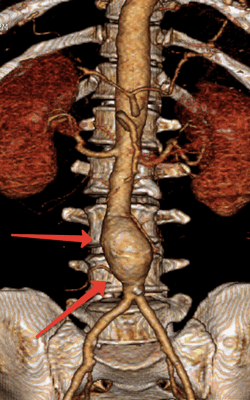

3D-реконструкция аорты - брюшной отдел и бифуркация

Аневризматические расширения брюшной аорты обозначены стрелками